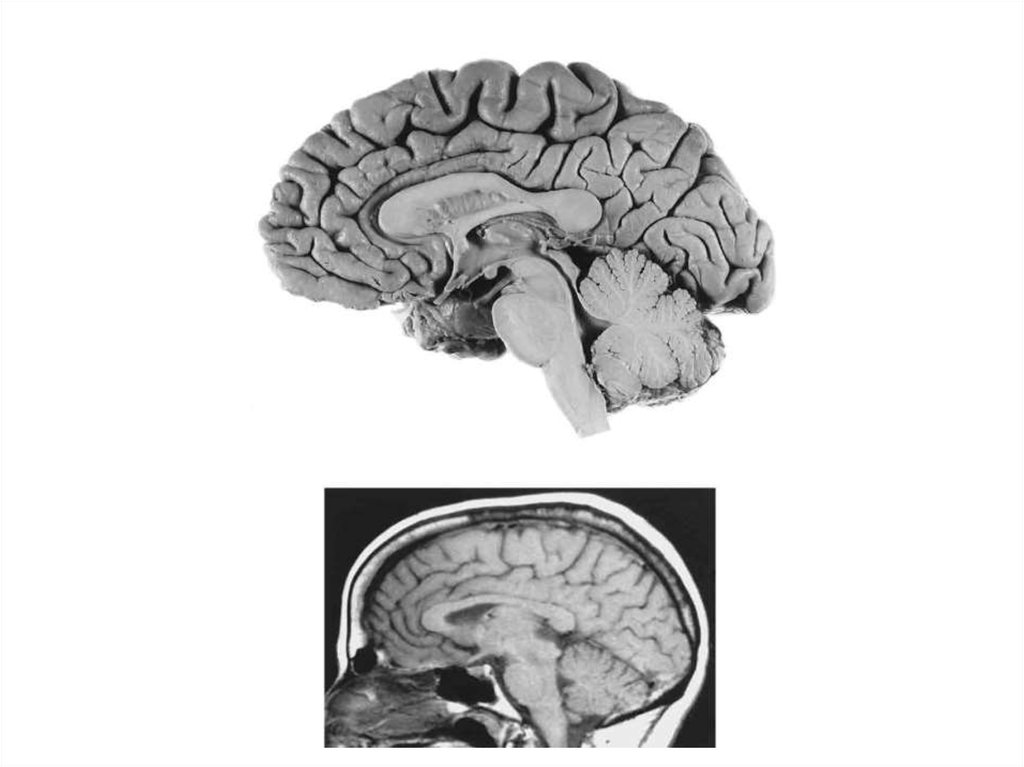

7. Полости СМ и ГМ

1. Четыре желудочка ГМ:

- 1-й и 2-й (боковые) в правом и

левом полушарии конечного

мозга

- 3-й в промежуточном мозге

- Сильвиев водопровод в

среднем мозге

- 4-й в продолговатом и заднем

мозге

2. Центральный спинномозговой канал (СМ)